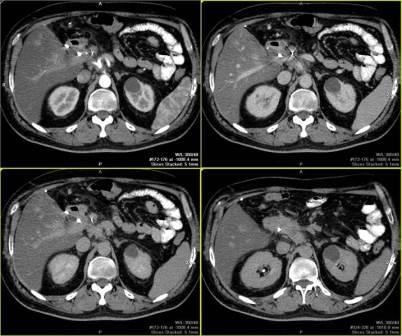

Multislice CT permite investigarea regiunii anatomice într-o perioadă de întârziere de respirație și de a schimba etapa de reconstrucție în prelucrarea ulterioară a datelor.

Obținerea secțiuni subțiri vă permite să creați de reconstrucție tridimensională.